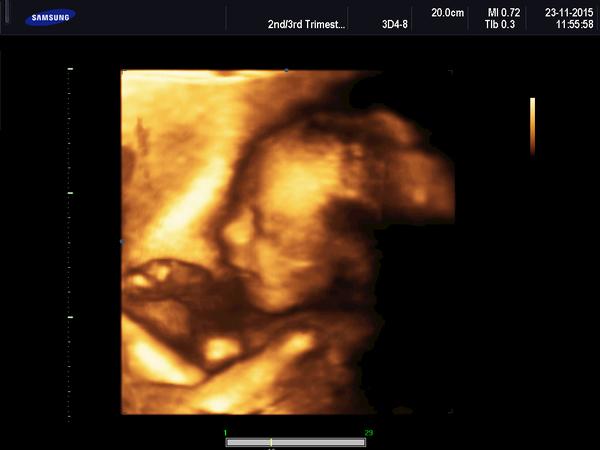

@briketaaaa krásná fotecka😊

@briketaaaa krásna foto 🙂..,gratuluji už ted je nádherný 😉

@briketaaaa Ten je krásný😊vypada moooc spokojene,nam udelaji 4D az po 20tt u dvojčátek😊